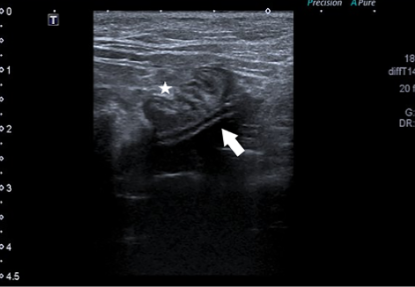

말로 설명하면 무슨 말도 안되는 소린가 싶기에 논문에 나오는 예시 사진을 보면 아래와 같다.

초음파로 plication 까지 발생한 환자의 영상이나 이는 운이 좋아 진단하는 case로 생각되고 실제 진단이 쉽지는 않을것이다.

특히 협조력이 떨어지는 고양이에서는 더더욱 검사가 어려울 수 있는데 그나마 다행인것은

flushing bell을 통해 조영제를 주입하면 이렇게 migration된 끝단이 확인될 수 있으니 이 방법으로 체크해 보는게 추천된다.